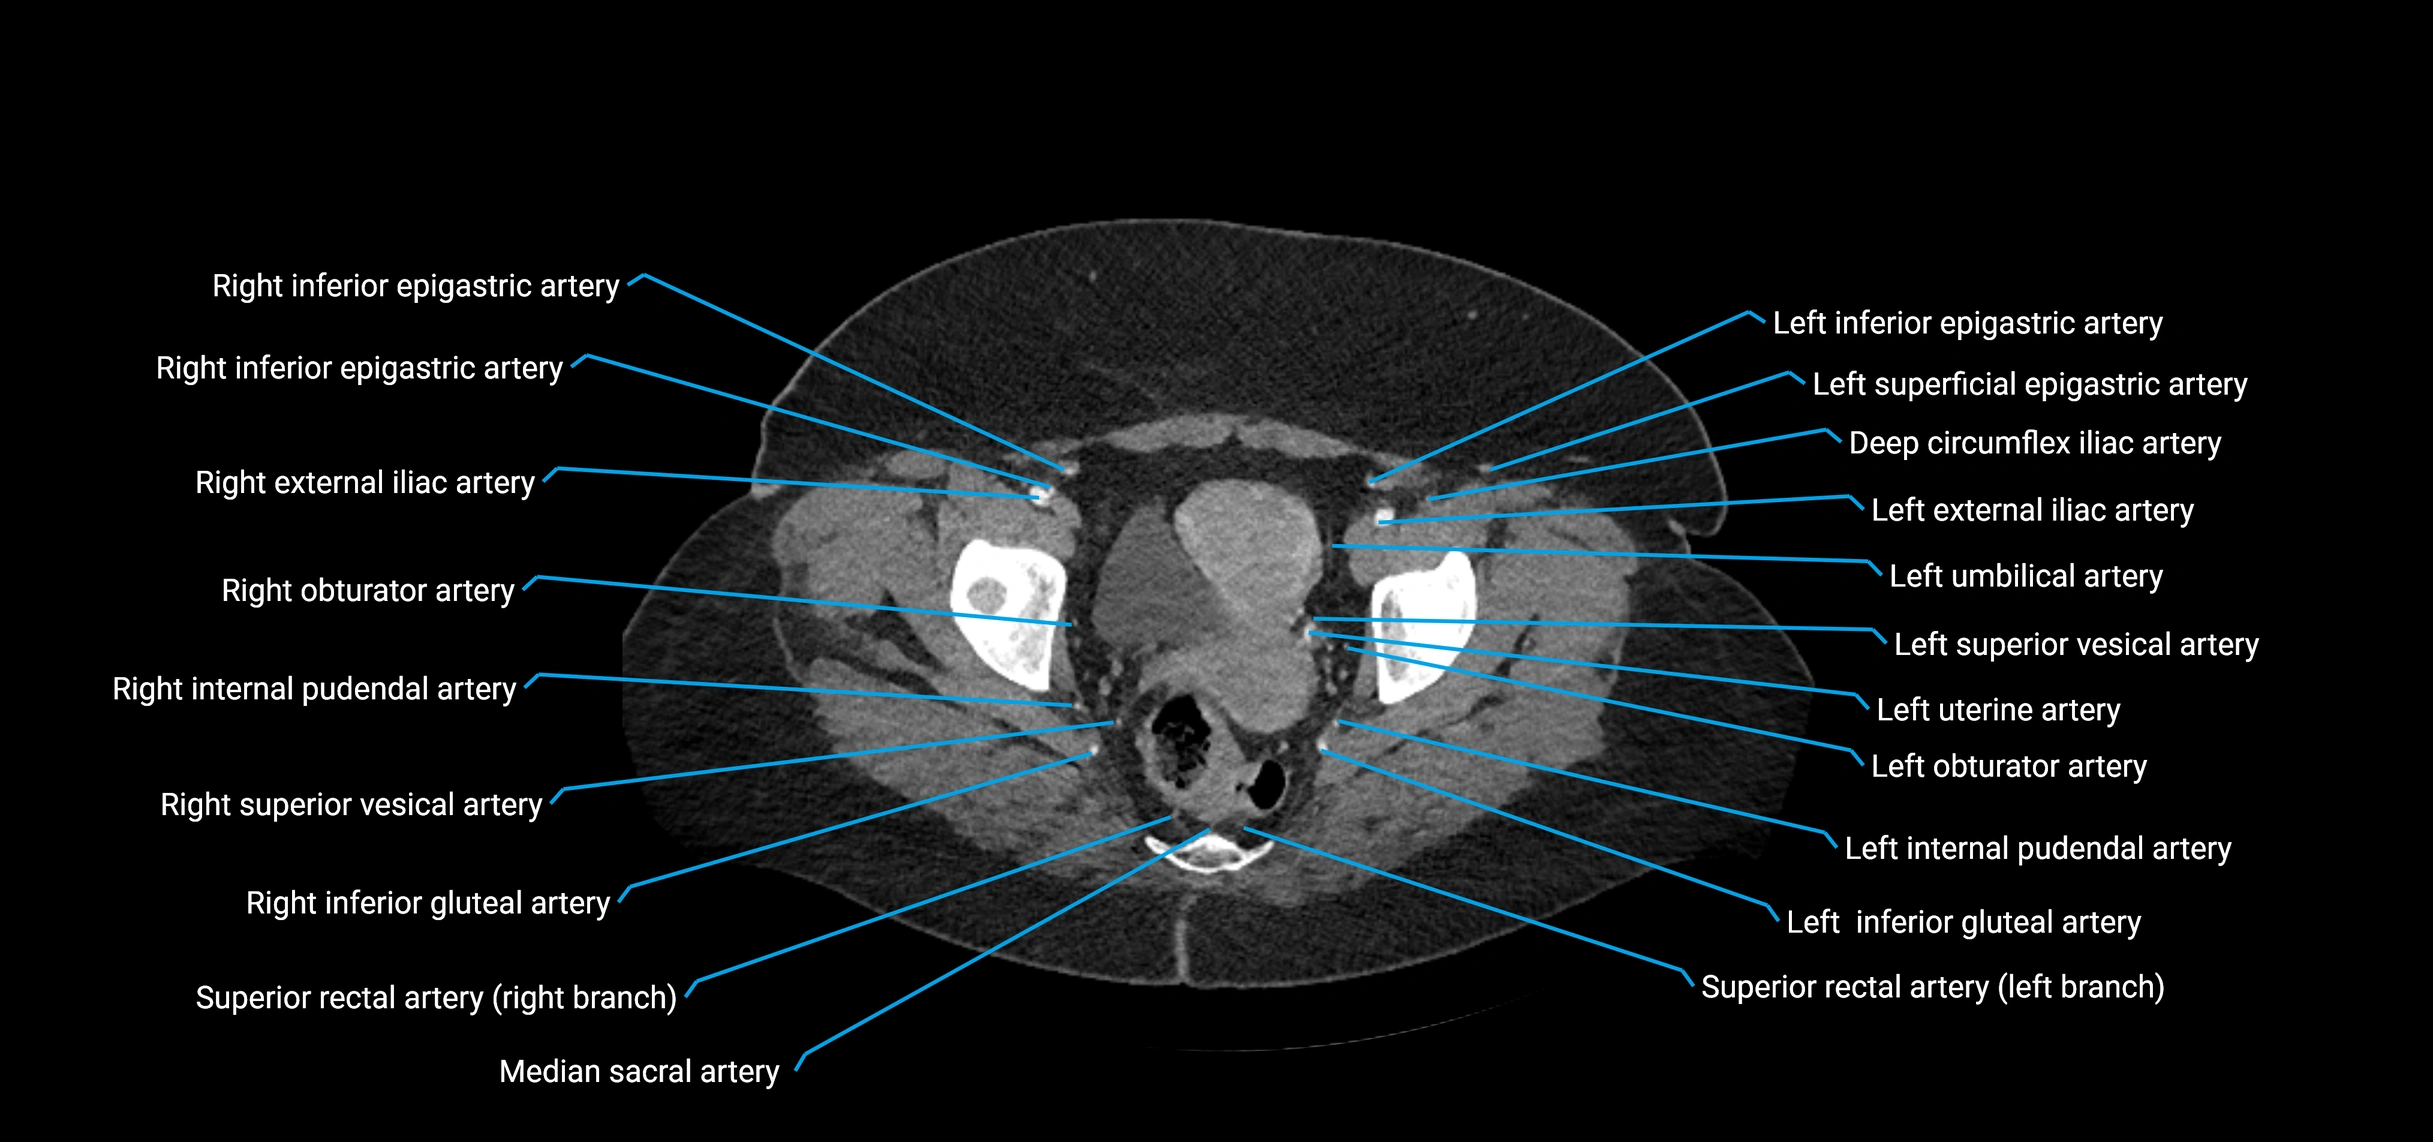

Contrast-enhanced CT (CTA):

• Gold standard for abdominal aortic imaging

• Provides excellent detail of lumen, wall, aneurysm, thrombus, and branch vessels

• Multiplanar and 3D reconstructions help in aneurysm measurement, stent graft planning, and dissection evaluation

• Detects acute rupture, traumatic injury, or occlusion with high sensitivity